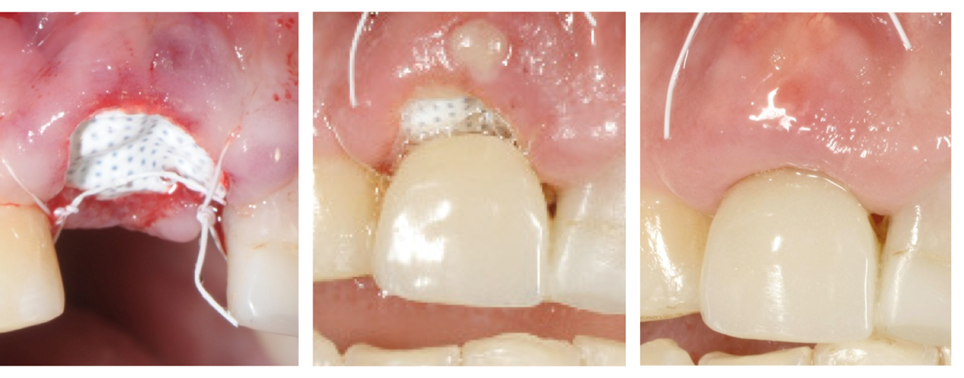

La membrana Cytoplast in d-PTFE viene ritagliata per estendersi di 3-4 mm oltre i margini della cavità e quindi con un curette infilata sotto il periostio del lembo palatale, vestibolare e la papilla interdentale.

La membrana viene ulteriormente stabilizzata usando una sutura incrociata in PTFE Cytoplast®. In alternativa si possono posizionare dei punti interrotti. Le suture in PTFE, che causano una risposta infiammatoria minima, vengono lasciate in sito per 10-14 giorni.

La membrana viene rimossa in modo non chirurgico dopo 3-4 settimane. Gli studi hanno infatti dimostrato che in tale periodo si forma una matrice di tessuto connettivo denso e vascolarizzato e una prima osteogenesi viene osservata nei 2/3 della cavità.

Dopo 6 settimane la gengiva cheratinizzata ha iniziato a formarsi sopra la cavità che è stata riempita. La naturale architettura del tessuto molle è preservata, incluso la papilla interdentale.

Tre momenti: al momento della chirurgia, dopo 1 settimana e dopo 4 settimane